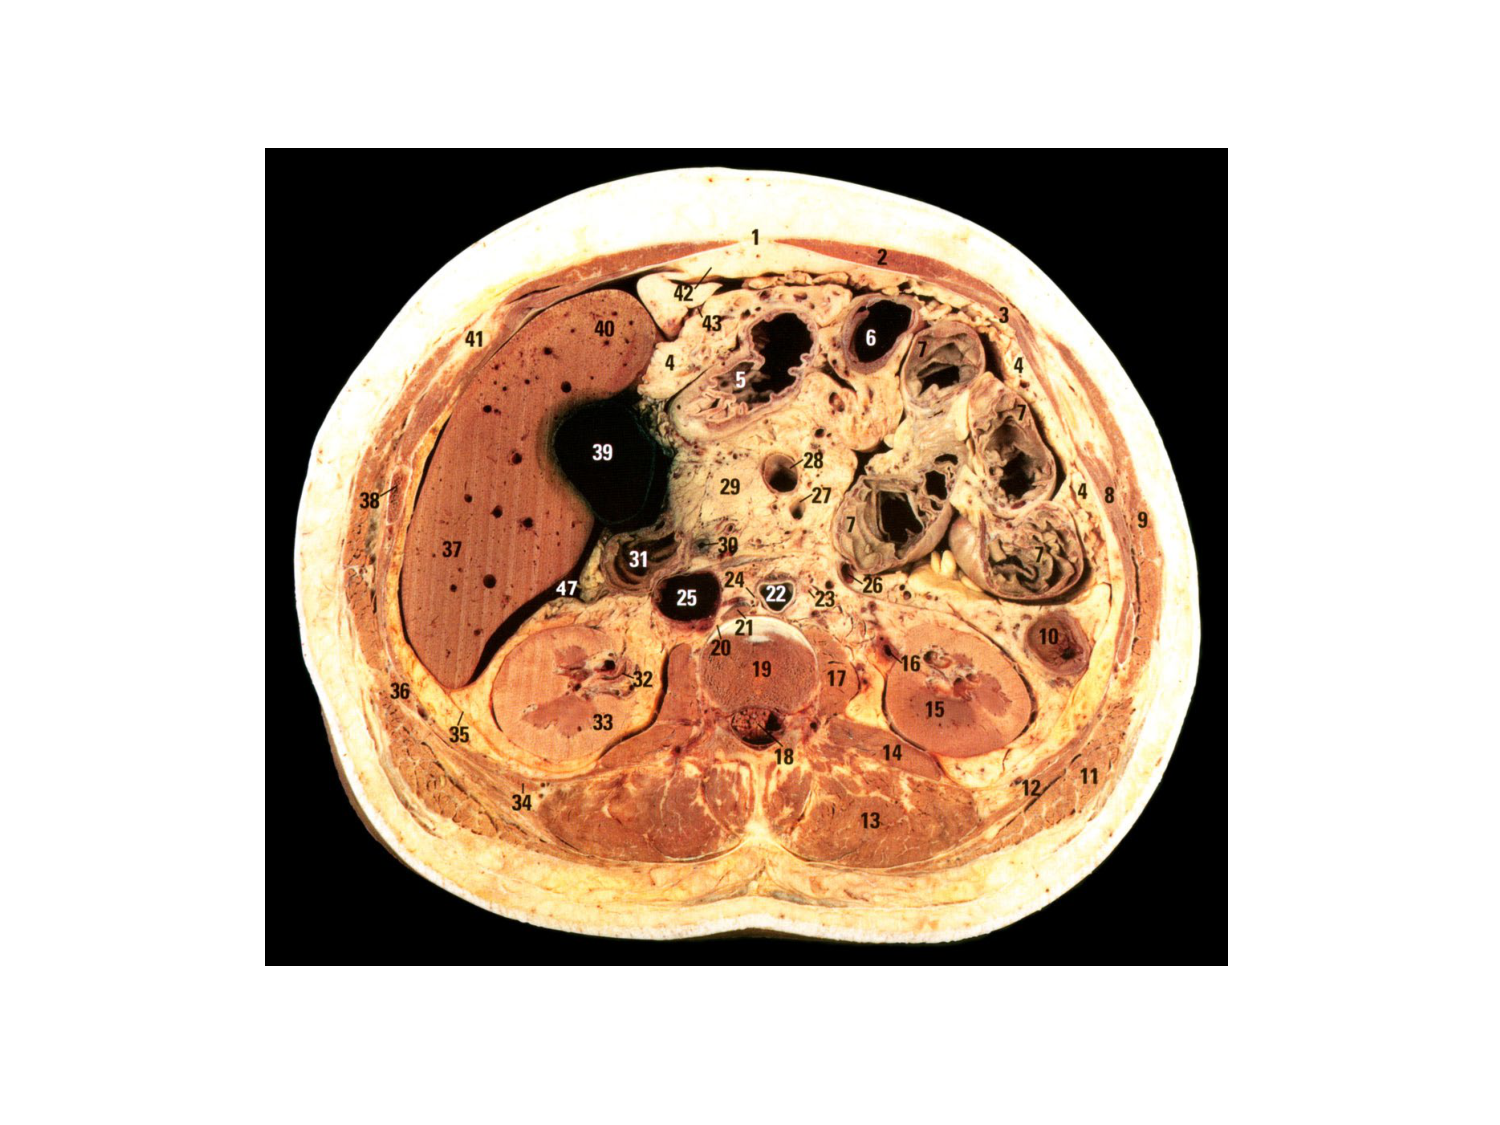

11.47 · Rein, voies urinaires et retropéritoine

Rein, voies urinaires et retropéritoine